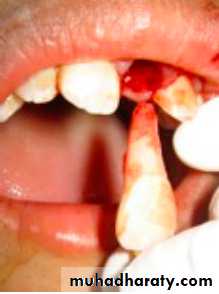

1-Tooth Avulsion

Definition:

Is a Complete displacement of tooth out of socket, The periodontal ligament is severed and fracture of the alveolus may occur.

Maxillary Central Incisor- Most commonlyavulsed tooth

Mandibular Teeth- Seldom affected

Most frequently involves a

single tooth

Most Common age-7 to 11

Permanent incisors erupting

Loosely structured PDL